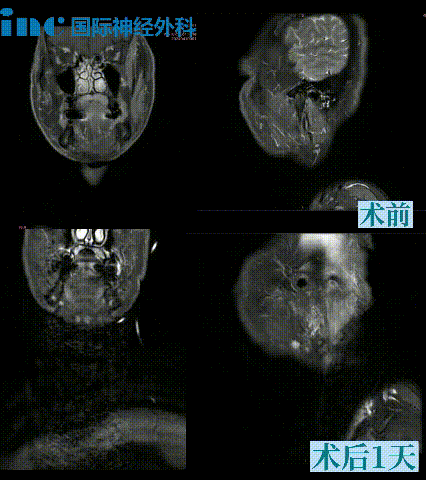

2024年4月,巴教授示范手术期间,就有一名来自东南亚的颈静脉孔区神经鞘瘤患者。38岁男士Norodom,东南亚不远万里来华求医。1个多月前,Norodom意外查出颈静脉孔区神经鞘瘤,症状不断加重。频繁呛水,颈部右倾,右肩肌肉僵硬,持续右侧颈痛,只能右侧卧……在经过多方打听后,Norodom在家人的陪同下,专程坐飞机来到中国,慕名求医。然而,却被告知手术后可能出现并发症,包括声音变沙哑、吞咽困难和呛水等。如预期一般,示范手术成功。术后1天ICU内查房,Norodom意识清醒,吞咽功能正常,肢体活动正常。

45岁男性,眩晕1年为主诉入院。左侧外展、面、听神经功能障碍。在MRI上(图1),发现一个较大的颈静脉孔肿瘤向颅内外延伸。病人选择巴特朗菲教授手术,教授通过左侧扩大经髁入路。肿瘤被完全移除了。组织学检查发现是神经鞘瘤。术后过程平安无事。术后2年随访,肿瘤未复发。

图示:术前MRI显示左侧颈静脉孔较大占位,颅内外延伸,术后确诊神经鞘瘤,术后2年复查MRI显示肿瘤完全切除且没有复发